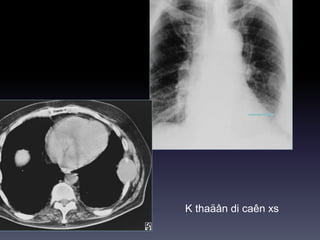

K thaäân di caên xs

(Osteochondroma) Beänh Kahler

U XÖÔNG &PHAÀNMEÀM Hình CT -Huûy, bieán daïng xöông / Toån thöông phaàn meàm/ Xoùa lôùp môõ ngoøai maøng phoåi (+/- ) -Caàn khaûo saùt coù caûn quang. Vai troø CT -Ñaùnh giaù toát vò trí, möùc ñoä, lieân quan toån thöông vôùi caùc caáu truùc khaùc ngöïc (phoåi, maøng phoåi, trung thaát)

K thaäân dicaên xs